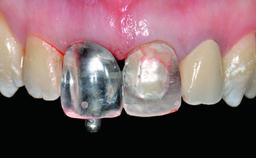

A 49-year-old female patient was referred for implant therapy to replace the upper right central incisor (tooth 11). The tooth had been assessed by an endodontist who diagnosed a vertical fracture of the root. The tooth had a hopeless prognosis and needed to be extracted. The patient was healthy and was not taking any medications. She was allergic to penicillin. The patient had high esthetic demands but her expectations were realistic. The extraoral examination revealed no facial asymmetries. The right temporomandibular joint demonstrated an opening click but was otherwise asymptomatic. The lip line was high with a significant gingival display.

Loading Protocol Conventional or early

Provisional Implant-Supported Prosthesis - -

Interim Prosthesis during Healing Removable Removable